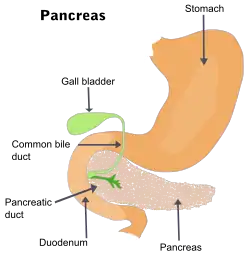

The pancreatic duct, or duct of Wirsung (also, the major pancreatic duct due to the existence of an accessory pancreatic duct), is a duct joining the pancreas to the common bile duct. This supplies it with pancreatic juice from the exocrine pancreas, which aids in digestion.

The pancreatic duct joins the common bile duct just prior to the ampulla of Vater, after which both ducts perforate the medial side of the second portion of the duodenum at the major duodenal papilla. There are many anatomical variants reported, but these are quite rare.[2]

Accessory pancreatic duct

Most people have just one pancreatic duct. However, some have an additional accessory pancreatic duct, also called the Duct of Santorini. An accessory pancreatic duct can be functional or non-functional.[3][4] It may open separately into the second part of the duodenum,[3][4] which is dorsal, and usually (in 70% of people) drains into the duodenum via the minor duodenal papilla. In the other 30% of people, it drains into the main pancreatic duct, which drains into the duodenum via the major duodenal papilla. The main pancreatic duct and the accessory duct both eventually—either directly or indirectly—connect to the second part ('D2', the vertical segment) of the duodenum.